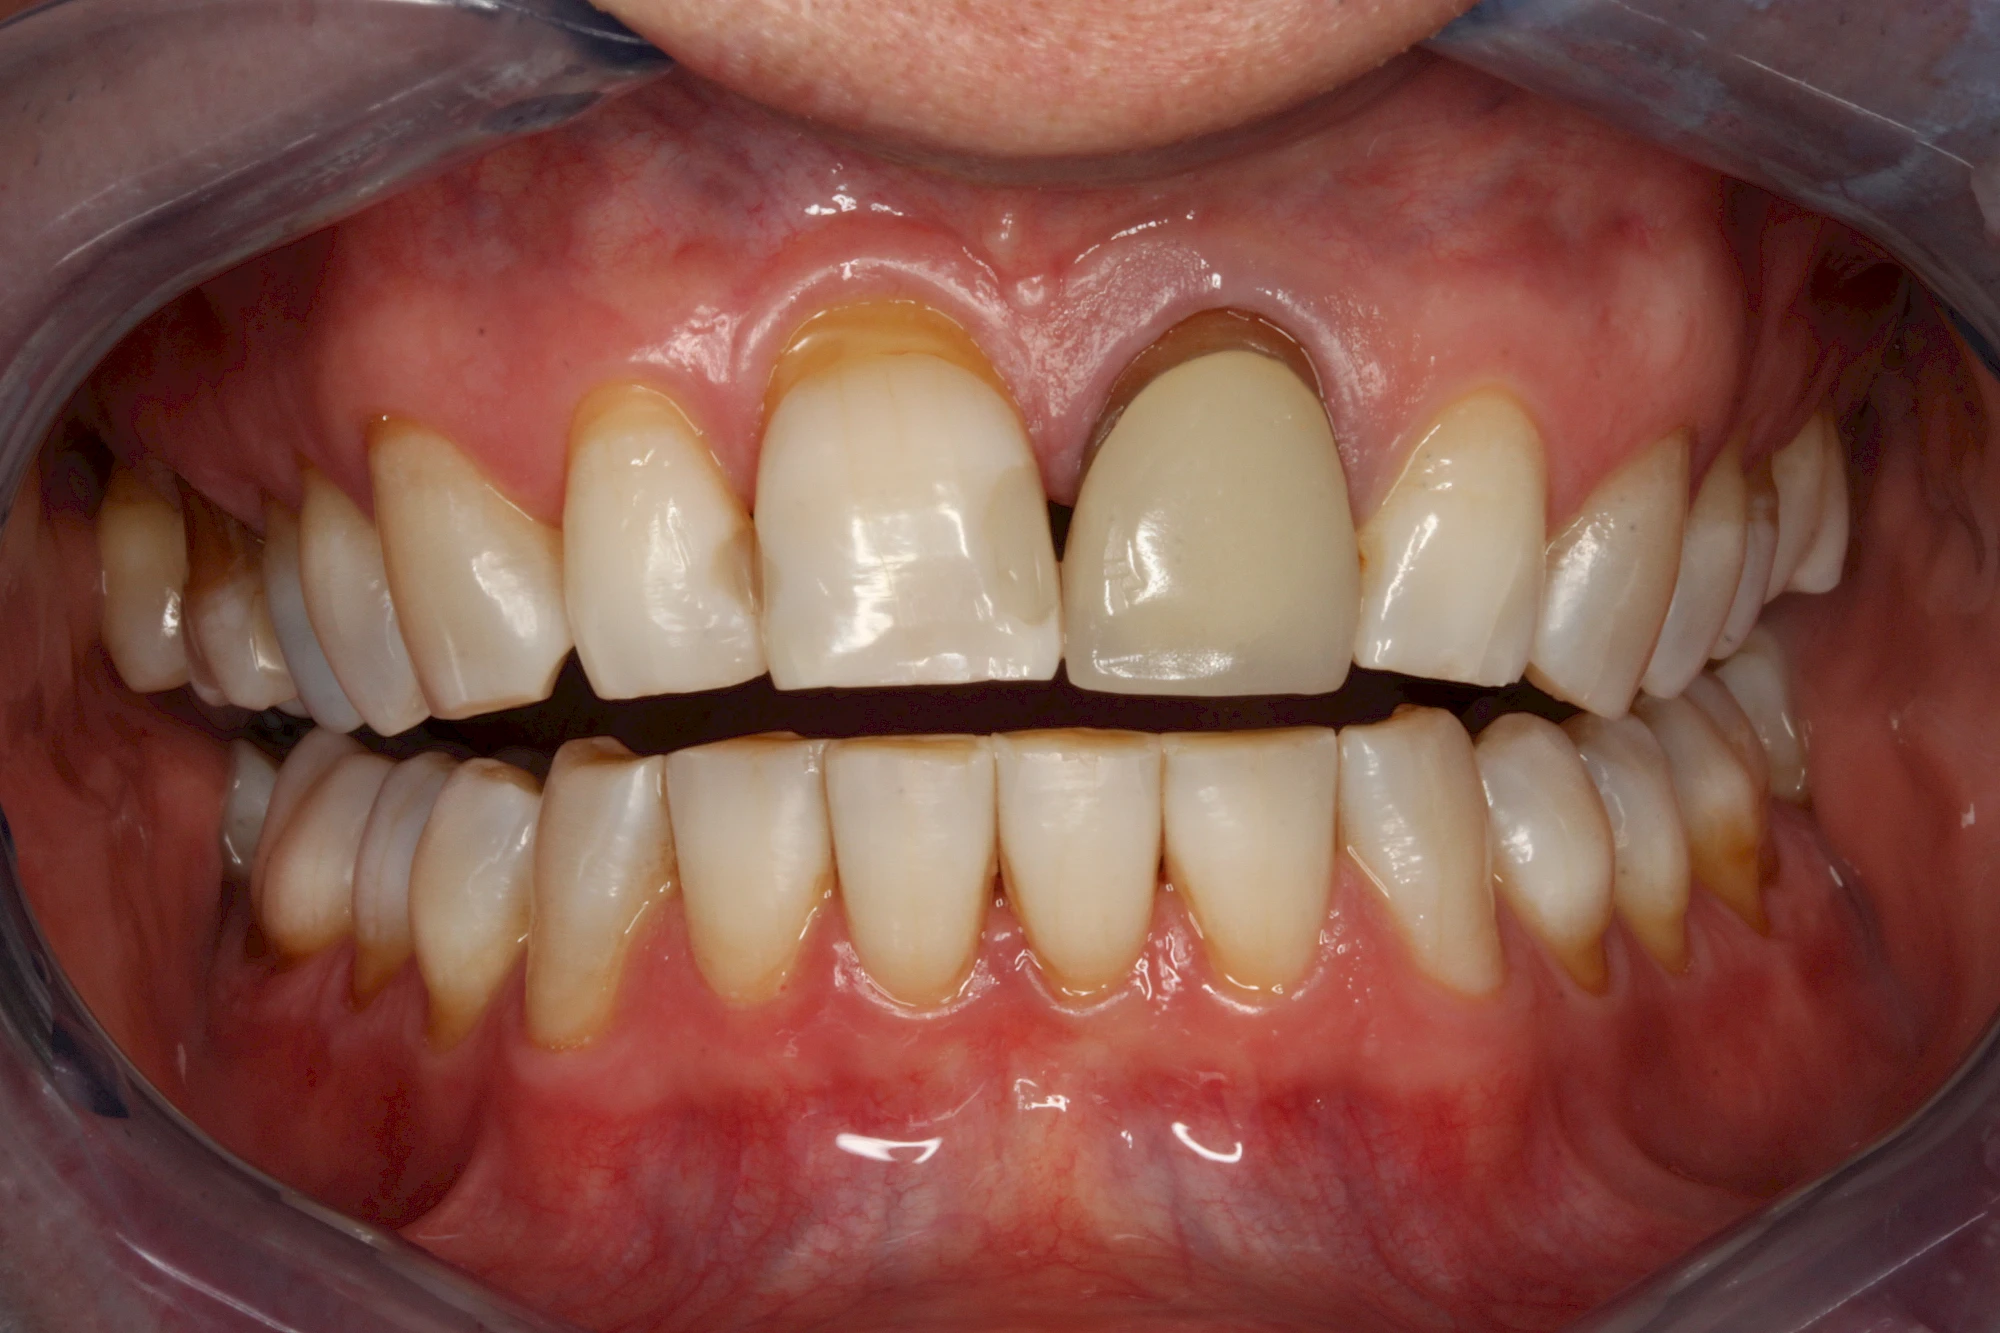

- Durch Blutabbauprodukte, weil der Zahnnerv abgestorben (einzelner Zahn, dunkel-flächig)

Äußere Verfärbungen durch Genußmittel oder Medikamente (Eisen!) lassen sich meist nur durch den Zahnarzt z. B. mit einer professionellen Zahnreinigung entfernen.

Ist ein einzelner Zahn deutlich dunkler als die Nachbarzähne kann das ein Zeichen sein, dass der Nerv abgestorben ist. Unter Umständen wurde bereits eine Wurzelkanalbehandlung vom Zahnarzt durchgeführt. Eine Abklärung durch den Zahnarzt ist in jedem Fall sinnvoll.